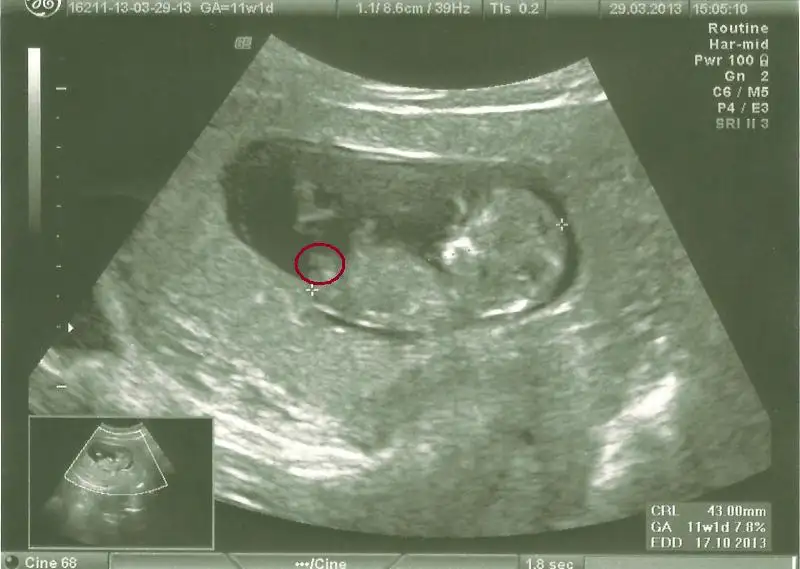

$11w1d (2).webp

orkidecim canım bu kırmızıyla işaretlediğim yer nub çıkıntısı mı ayak mı

bence nub çıkıntısı, sen ne dersin, sen daha iyi bilirsin tabii canım

ayak diyor snnemlerde bence ayak değil ayağı yukarda sanki

Yukarıda olan bacak yuvarlak içine aldım ama görünüyor mu acaba?:18:

paralel olup erkek cikanda cok oldu bak gecenki fotosuda dikeydi

ama hakikattenn nub cok buyuk erkege donecek nublar gibi ama asagida olmasi beni huzunlendiriyor :5::5::5:

yaaa bak o cizdigin yuvarlagin altinda hemen dikey kucuk bir cikinti var eger oysa ki insallahh diyeelim o zaman kesin erkekk :43:yaa iki cikintisi var bebegin